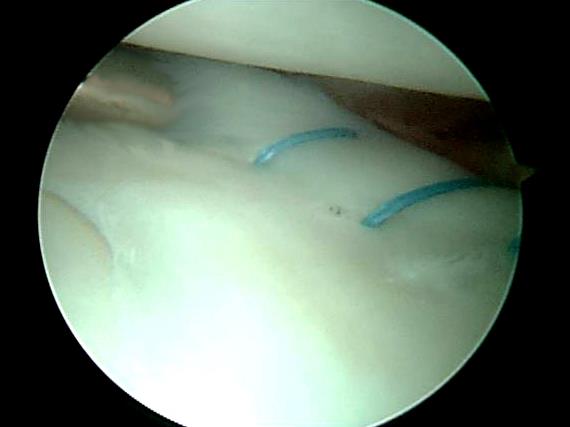

半月板內窺鏡手術主要分為兩種:1. 切除術2.修補術。半月板外圍是帶有血管的部份,如果作修補術,效果比較滿意。但如果是中心位置的撕裂,由於天生那部份是沒有帶血管的,就算修補也不能癒合。這時便需要進行切除撕裂的半月板,再把披口打磨光滑。

半月板修補術示意圖

內窺鏡所見之半月板修補術